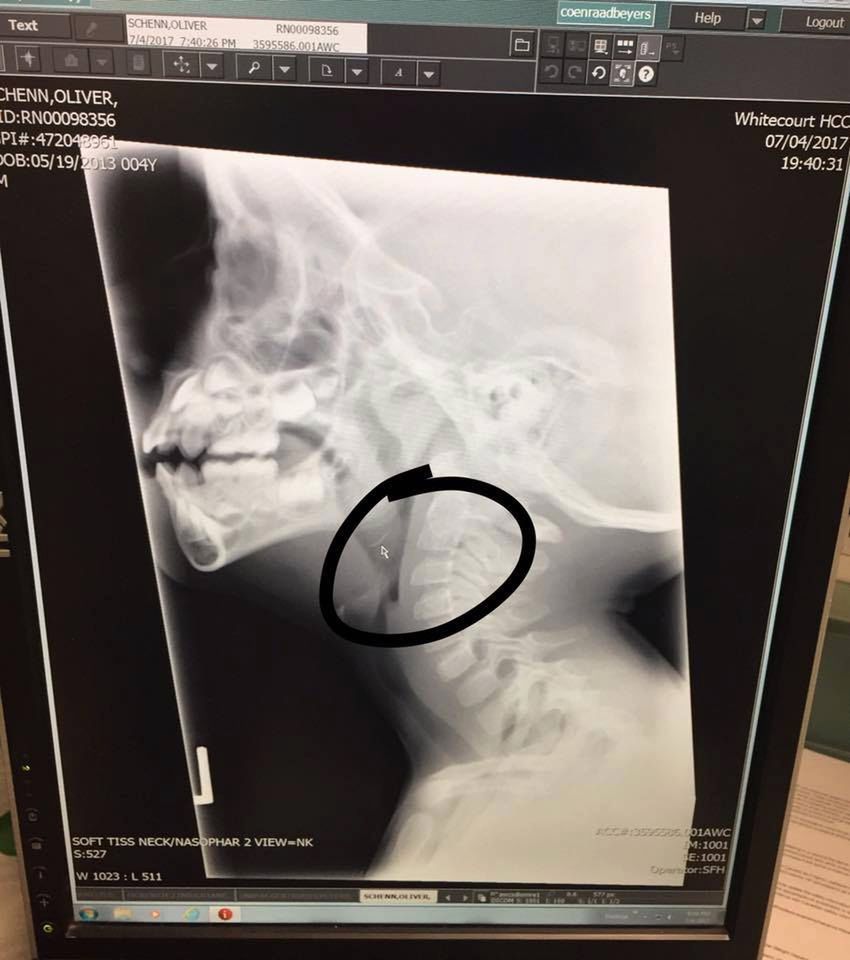

Metalowe elementy szczotki czyszczącej! Okazało się, że kolejne kawałki kurczaka też je miały. Zrobione po dwóch godzinach prześwietlenie mojego synka potwierdziło nasze obawy. Ollie nie mógł przełykać!

Mały Ollie połknął kawałek metalu

Mały Ollie połknął kawałek metalu © Facebook @Jenna Kuchik